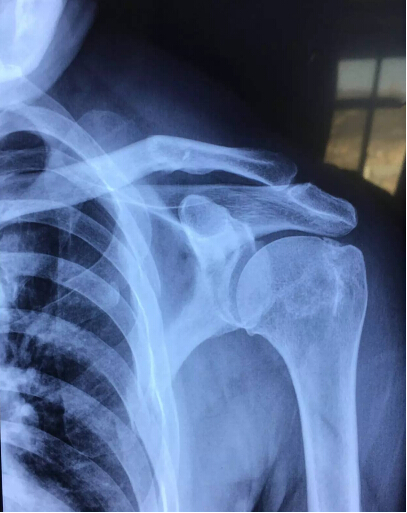

術(shù)前影像